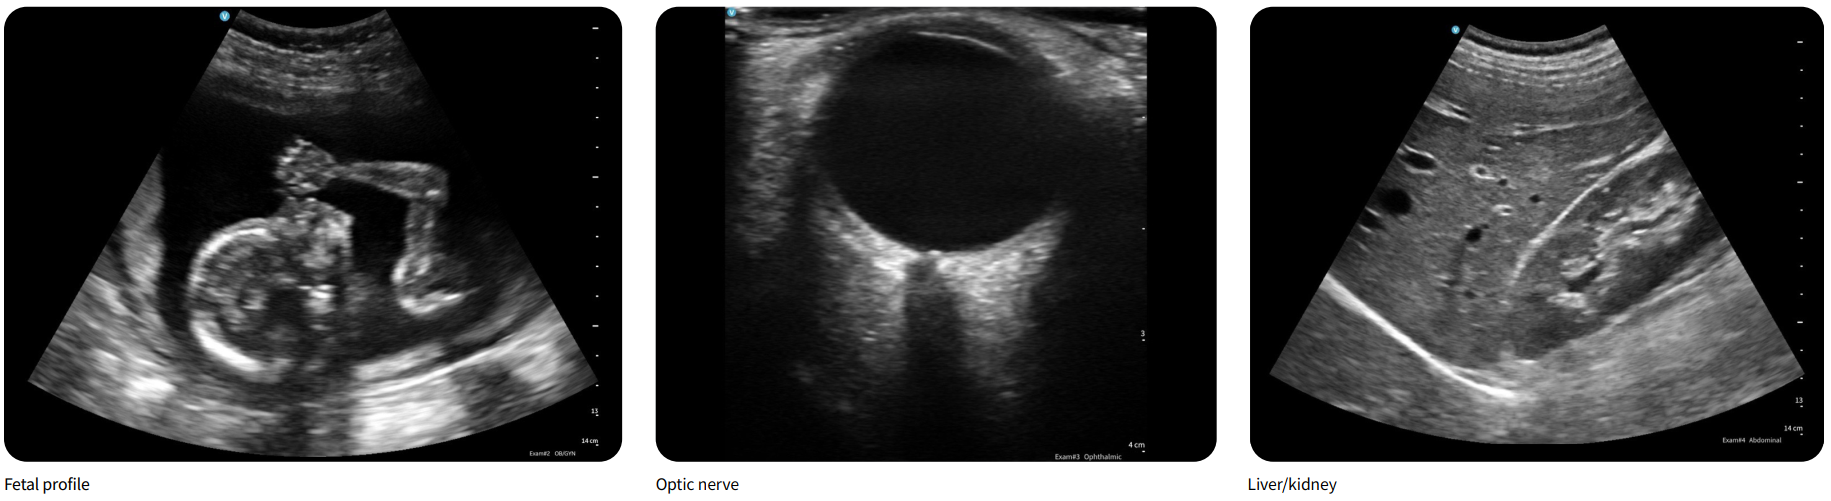

Một nghiên cứu so sánh 6 thiết bị siêu âm cầm tay do các chuyên gia POCUS thực hiện cho thấy Vscan Air được đánh giá cao về chất lượng hình ảnh trong nhiều chế độ quét(1). Cụ thể, trong nghiên cứu của Perez‑Sanchez và cộng sự (The Ultrasound Journal, 2024), Vscan Air nhận điểm cao nhất ở phần quét vùng bụng (right upper quadrant)(2) và cũng được đánh giá cao nhất về độ dễ sử dụng.(3)

Một trong những điểm mạnh lớn của thiết bị siêu âm cầm tay Vscan Air là khả năng tái tạo hình ảnh với độ phân giải cao, đáp ứng tốt nhu cầu chẩn đoán trong thời gian thực. Thiết bị được tối ưu hóa cho các ứng dụng POCUS cho phép bác sĩ quan sát tổn thương mô mềm, mạch máu hoặc cấu trúc sâu một cách rõ nét và tin cậy. Điều này giúp tăng hiệu quả lâm sàng, đặc biệt khi quyết định điều trị cần đưa ra nhanh chóng ngay tại giường bệnh.

Sản – phụ khoa | Theo dõi thai, đánh giá cấu trúc tử cung, buồng trứng, mạch máu… |

Nội khoa & tim mạch | Quét tim, mạch máu, kiểm tra chức năng bơm máu; sử dụng cho bệnh nhân nặng hoặc nằm liệt giường. |

Cơ xương khớp & mạch máu | Phát hiện tổn thương mô mềm, dây chằng, gân, mạch ngoại biên ngay tại điểm chăm sóc. |